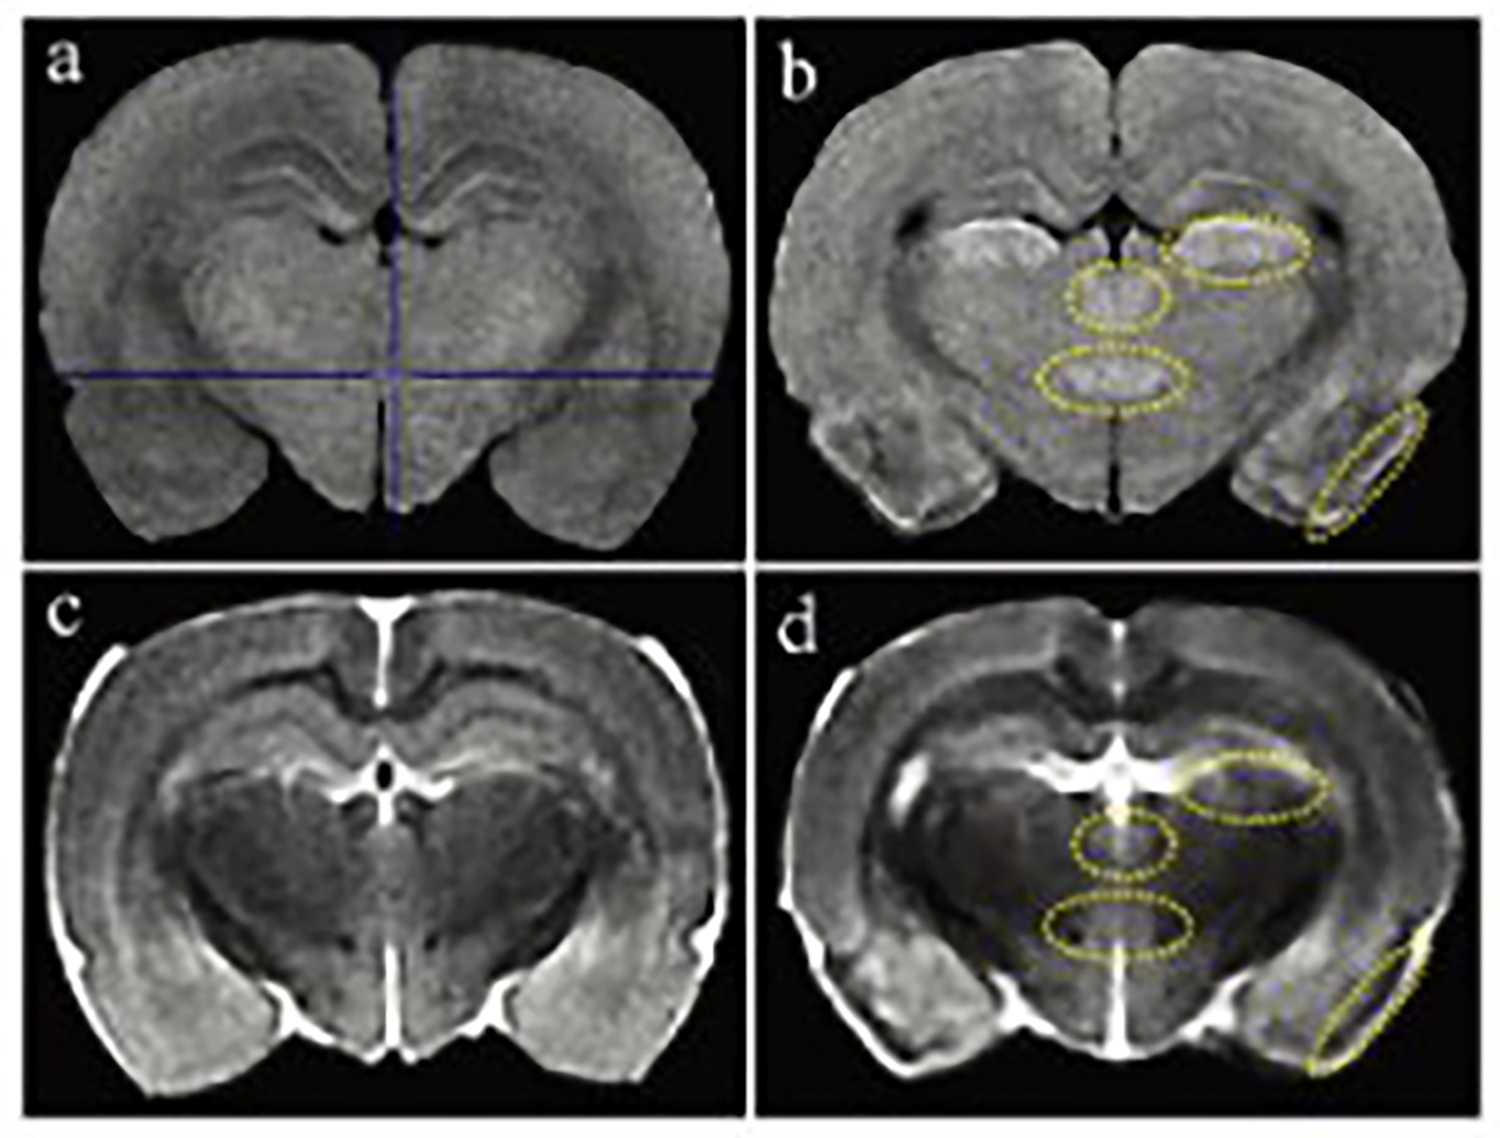

Dixon序列用于大鼠、小鼠水脂分离磁共振成像-脂肪抑制技术

低场核磁共振技术,已被广泛应用于小动物(大、小鼠)实验模型中,用于监测体内脂肪分布及沉积情况。这不仅有助于揭示人类肥胖代谢性疾病的病因,还为肥胖治疗药物的评价提供了重要依据。通过低场核磁共振技术结果表征,科研工作者能够直观地观察到小鼠体内脂肪的变化,从而更深入地理解肥胖症的发病机制。

Dixon脂肪抑制技术是由Dixon 提出,其基本原理是利用水、脂肪的化学位移差异,使用不同的回波时问,分别采集水和脂肪质子的in Phase 和 opposed -phase两种回波信号。